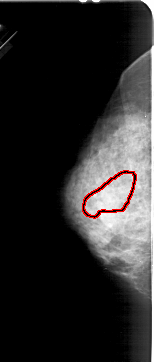

FILE: A_1538_1.LEFT_MLO.OVERLAY

TOTAL_ABNORMALITIES 1

ABNORMALITY 1

LESION_TYPE CALCIFICATION TYPE PUNCTATE DISTRIBUTION SEGMENTAL

ASSESSMENT 4

SUBTLETY 2

PATHOLOGY MALIGNANT

TOTAL_OUTLINES 1

BOUNDARY

LEFT_MLO LINES 5491 PIXELS_PER_LINE 2431 BITS_PER_PIXEL 12 RESOLUTION 43.5 OVERLAY